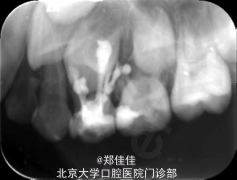

检查:64DO牙色充填体,边缘密合,叩痛(+),IO松动,颊侧牙龈肿包,未见瘘管,无扪痛 X线片示64根尖周低密度影,未见明显根吸收,下方24恒牙胚在,显示不全,表面硬骨板欠连续完整

初诊印象:64慢性根尖周炎处置:1.签知情同意书 2. 64DO必兰局麻下去部分旧充,开髓,揭顶,出血量多,色暗红,拔髓,不成形,2%CR荡洗,15#至40#K-file系列预备,纸尖擦干,螺旋充填器捣入Ca(OH)2糊剂,Ceivitron暂封。 3.刺破64颊侧牙龈肿包,见大量脓液,上碘甘油 4.医嘱,约日根充

5个月后拔除 讨论:乳牙慢性根尖周炎试留或拔除的临床决断 乳牙慢性根尖周炎可侵犯恒牙胚,一旦恒牙胚受侵犯是乳牙拔牙的重要指征。该病例就诊时乳牙牙根无明显根吸收,封Ca(OH)2两周后采用Vitapex根管充填治疗。vitapex 糊 剂 (日 本 森 田 株 式 会 社 )为氢氧化钙类制剂,主要成分为氢氧化钙,三碘甲烷,聚硅酮油。超出根尖孔部分数周内可吸收;急性根尖周炎时,可中和酸性脓液。国内有研究表明Vitapex根充糊剂在治疗乳牙根尖周病方面效果优于氧化 锌碘仿糊剂1。 经过近半年复查时发现该牙慢性根尖周炎累及恒牙胚,行拔除治疗,再次复查时恒牙已萌出约1/3。 【1】姚志荣,陈育纯,熊桂娟等.Vitapex糊剂在乳牙根管充填120例的临床观察[J].实用医技杂志,2011,18(2):189-190.